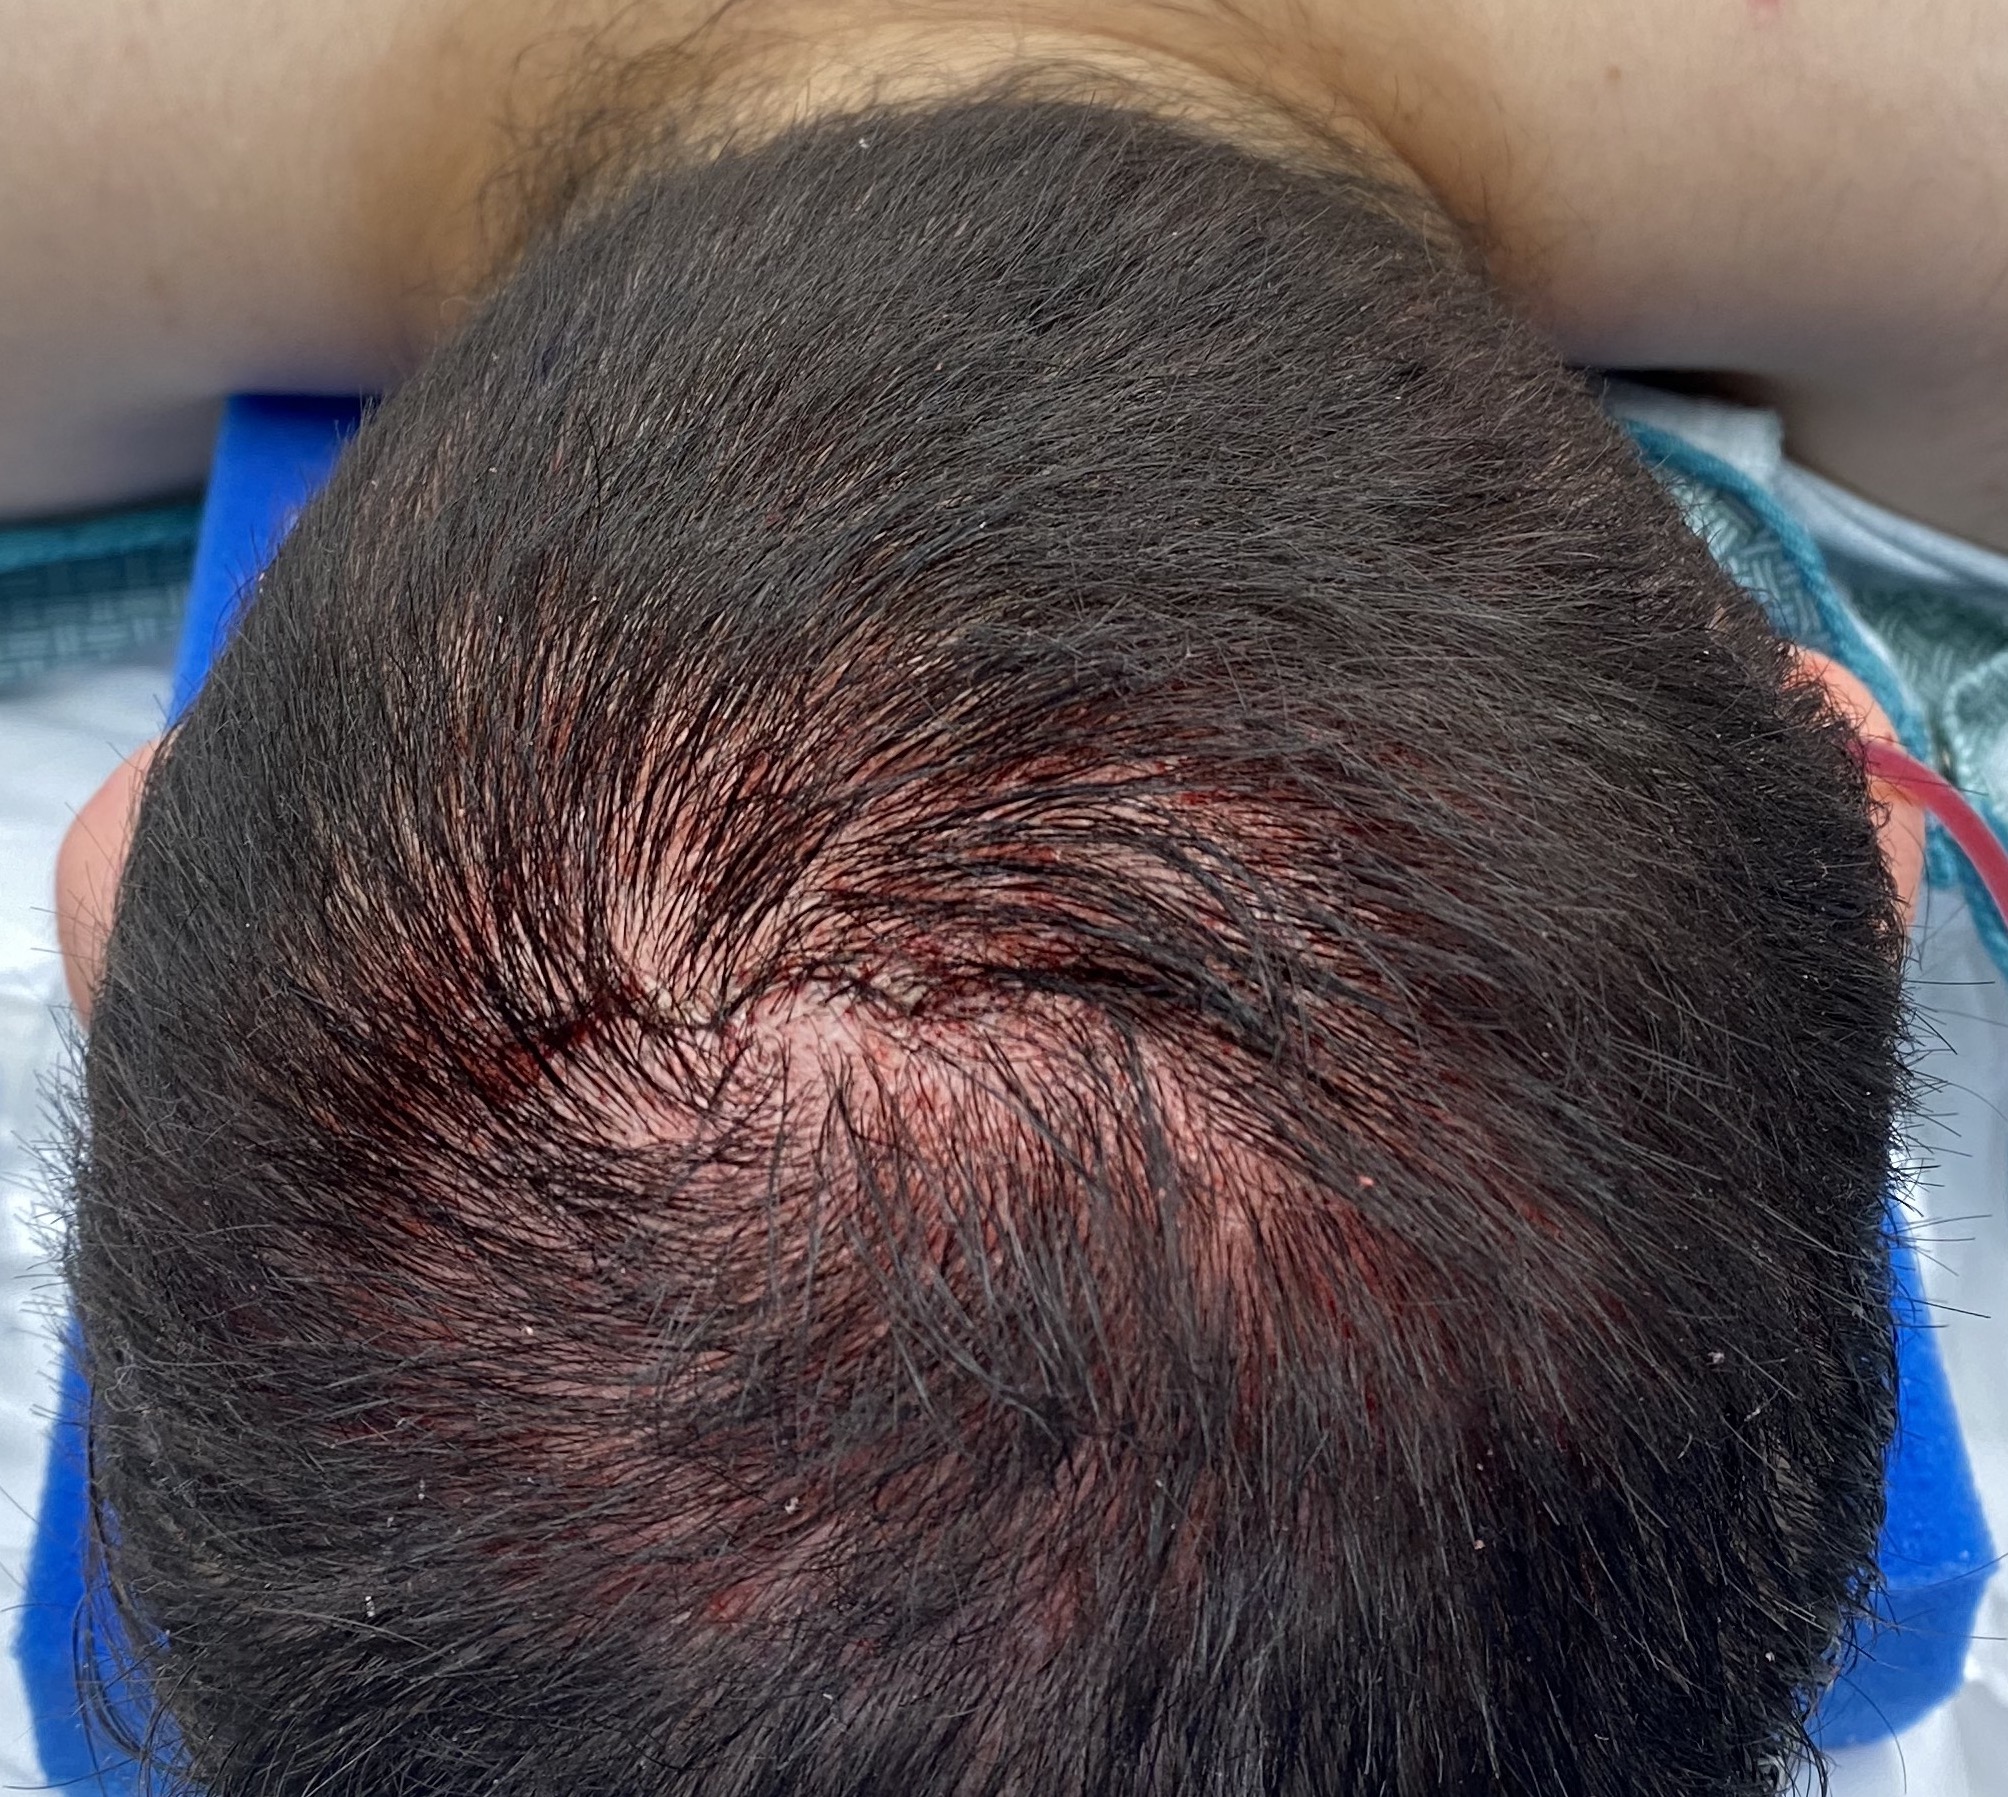

Patient 48

Removal of prominent midline sagittal bony ridge on top of head.

Reduction of posterior sagittal skull ridge through a small 3 cm scalp incision.

Removal of prominent midline sagittal bony ridge on top of head.

Reduction of posterior sagittal skull ridge through a small 3 cm scalp incision.